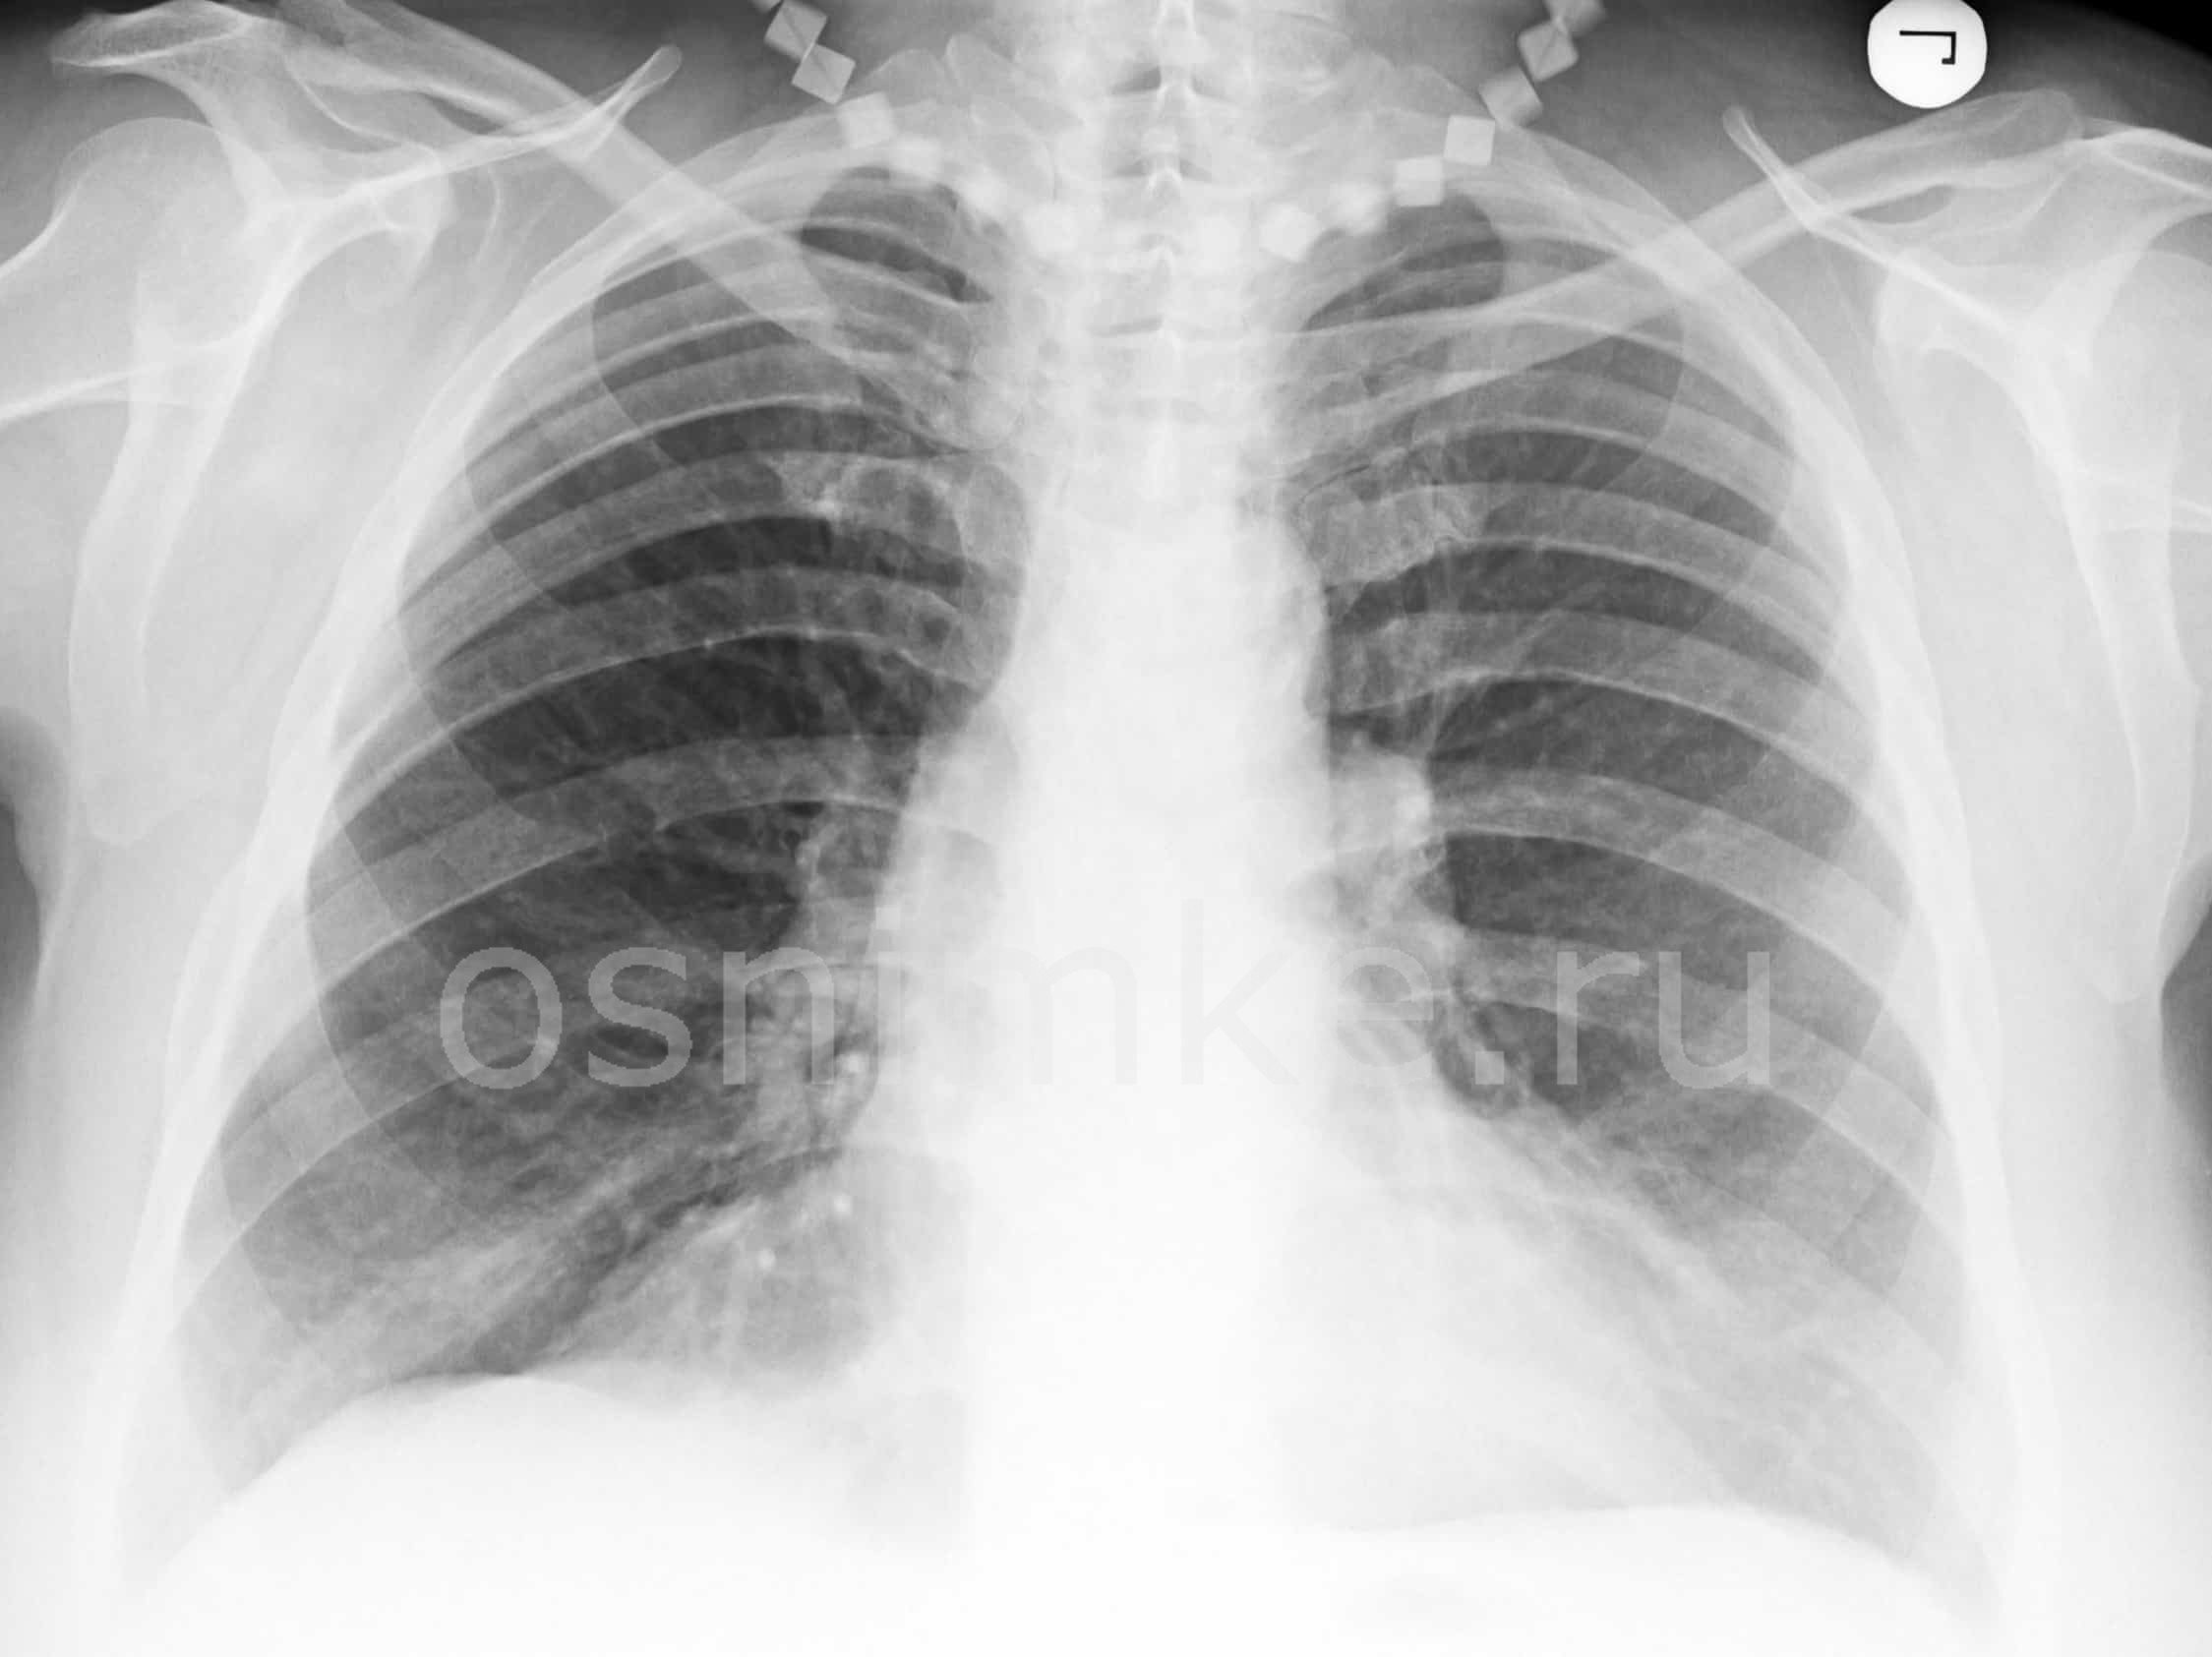

При атипичной пневмонии легких на рентгеновском снимке видны затемнения:

- мелкоочаговые – не более 3 мм;

- среднеочаговые – не более 7 мм;

- крупноочаговые – не более 12 мм;

- фокусные – более 12 мм.

Атипичная пневмония на рентгеновском снимке: